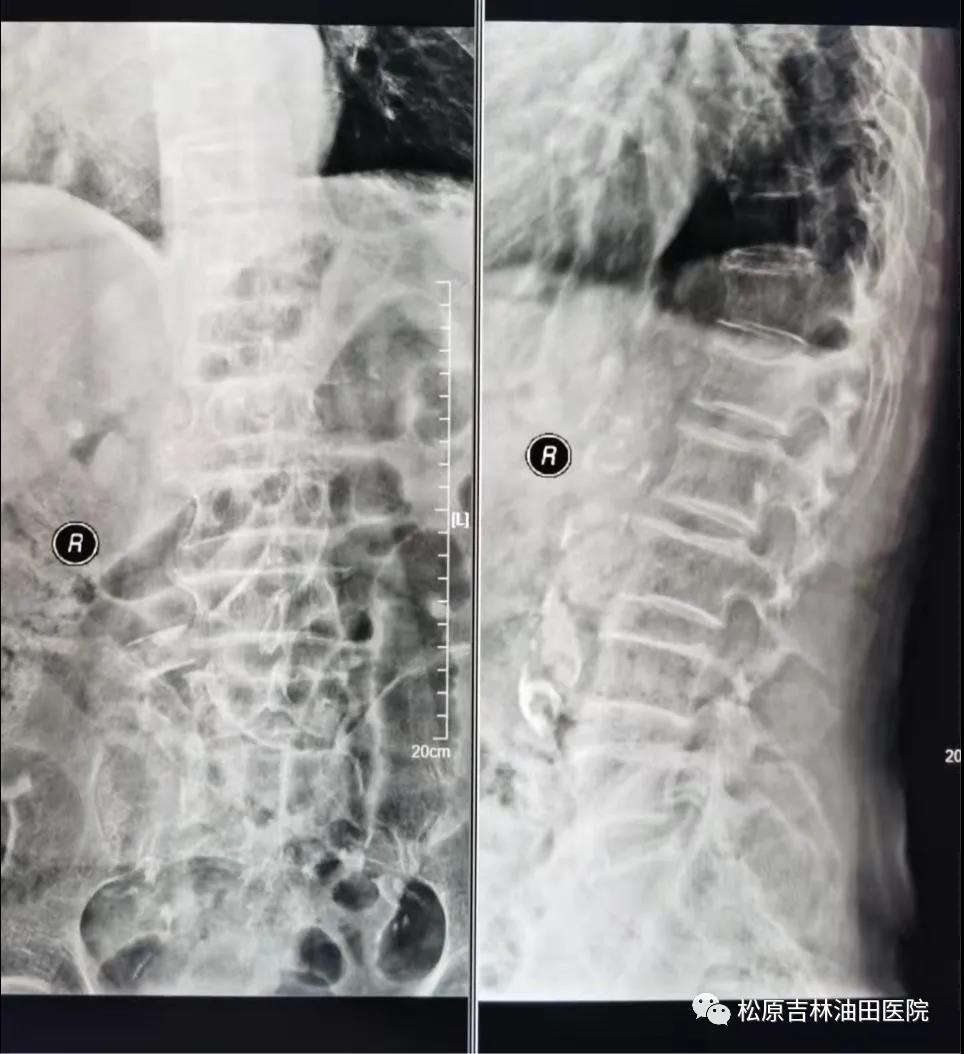

90岁老爷爷术前影像显示:腰1椎体压缩性骨折